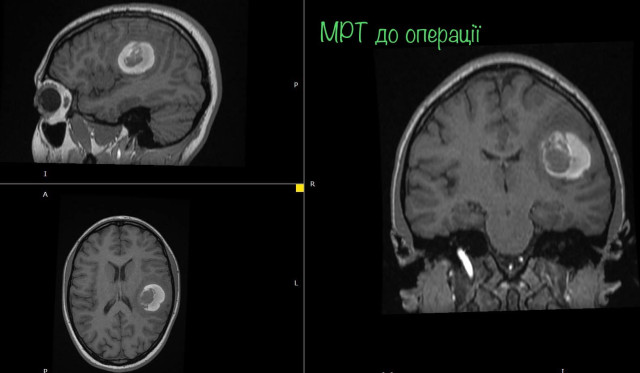

На МРТ виявили пухлину головного мозку з крововиливом в лівій домінуючій (важливішій) півкулі, в якій, власне, окрім центрів, які рухають кінцівками однієї половини тіла, розташований дуже важливий центр мови.